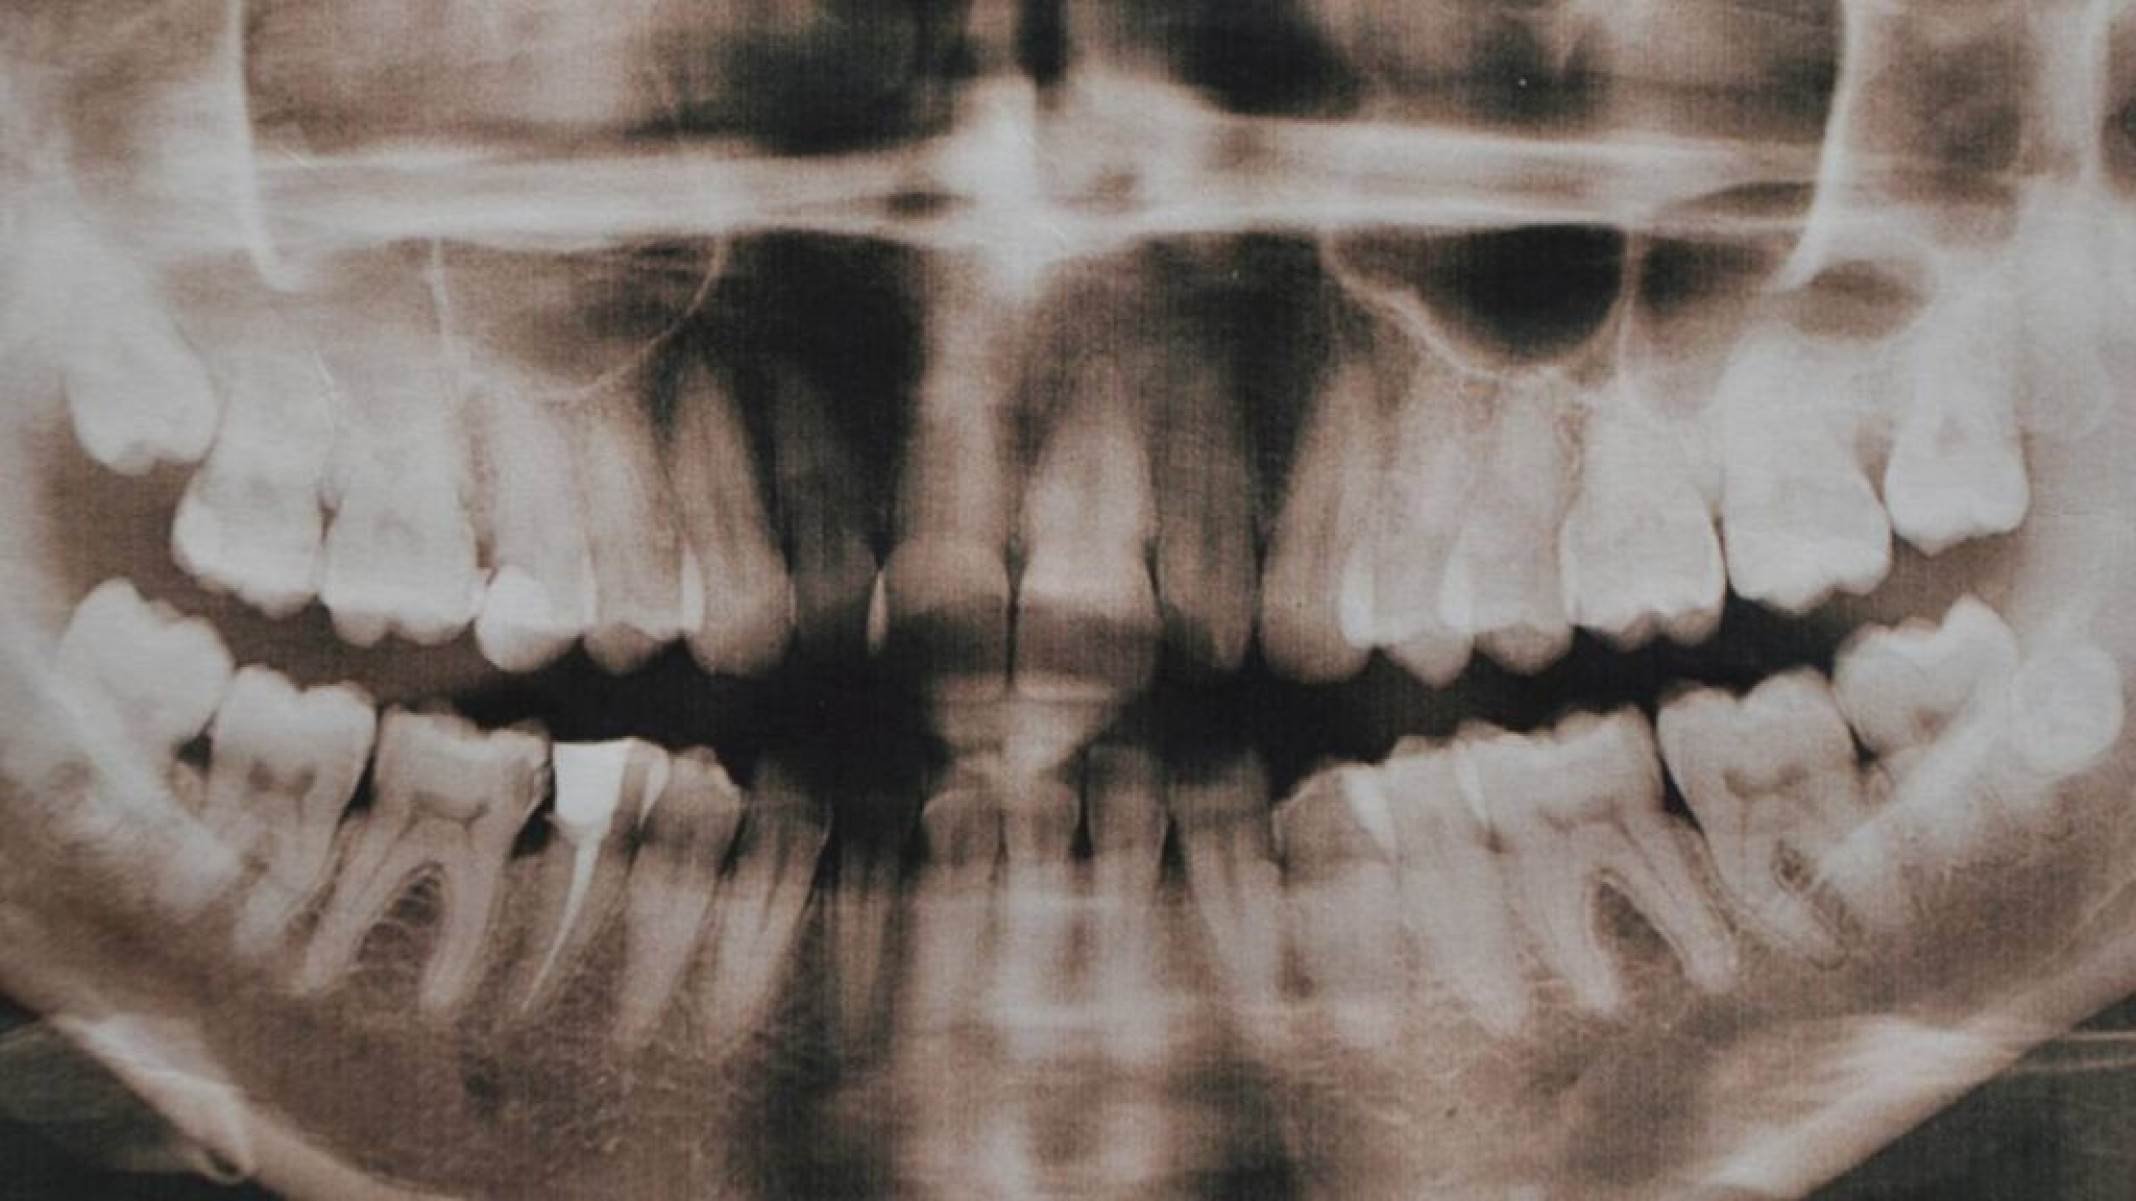

A hiperdontia é uma alteração do desenvolvimento dentário em que surgem dentes extras, os dentes supranumerários – depositphotos.com / YuliyaM

Clinicamente, a hiperdontia pode causar atraso na erupção dos dentes permanentes, desalinhamento, mordida cruzada e, em alguns casos, dor ou inchaço. Quando esses dentes supranumerários permanecem presos dentro do osso, a detecção costuma ocorrer em exames de rotina, como radiografias panorâmicas. Nestes casos, os dentistas as solicitam para acompanhar o crescimento craniofacial, principalmente na infância e adolescência.